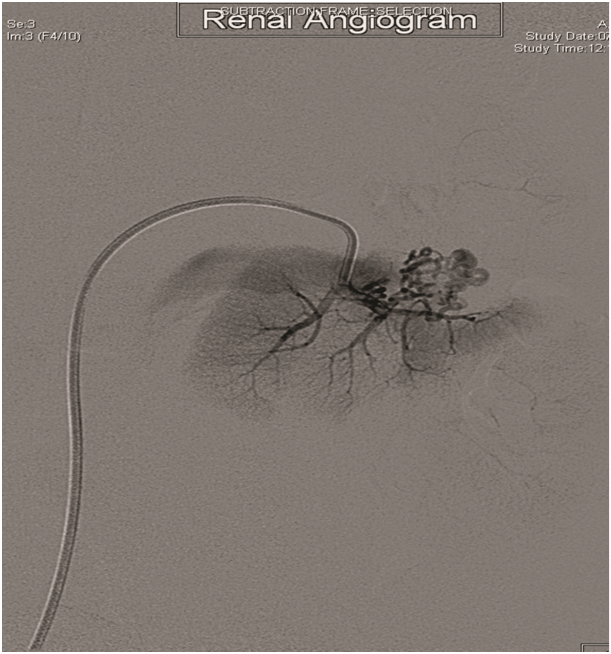

Selective left renal angiography by hand injection revealed a cork-screw like small renal vessels at inter polar region representing nidus of AV malformation with multiple feeding arteries associated with early draining to IVC (Figure 2). Selective embolization of AV malformation was done. Right common femoral artery was accessed with 6Fr sheath and 5Fr guide wire. Different angle angiogram showed multiple feeding arteries. The main Left renal artery feeding branches were occluded by embolizing material Onyx. There were no complications (Figure 3).

Figure 2 Left renal AV-malformation.